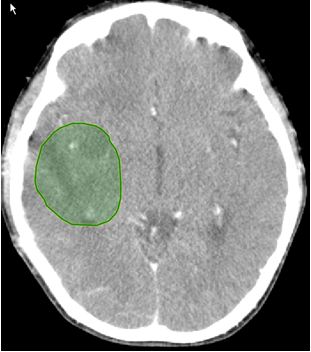

. Bệnh nhân được chẩn đoán: U não vùng thái dương bên phải; đã phẫu thuất lấy u tối đa; giải phẫu bệnh sau mổ: gliosarcome. Sau phẫu thuật cháu đỡ đau đầu nhưng vẫn yếu nửa người bên trái: cháu vẫn đi lại được. Tại TT YHHN&UB bệnh nhi đã được điều trị xạ trị gia tốc tổng liều 60Gy (1,5 Gy một ngày trong 40 ngày). Trong quá trình xạ trị thỉnh thoảng bệnh nhi có các triệu chứng tăng áp lực nội sọ như đau đầu, buồn nôn và nôn, và có sạm da vùng xạ trị mức độ nhẹ. Sau khi điều trị xạ trị gia tốc trên phim chụp cắt lớp vi tính sọ não hình ảnh khối u đã thu nhỏ kích thước hơn trước và có vùng hoại tử trong u.

Hình ảnh u trước điều trị: khối u vùng thái dương phải đường kính 5,5x4cm

Sau khi kết thúc điều trị: khối u đã thu nhỏ, kích thước hơn 3x2,5cm, hoại tử trong u